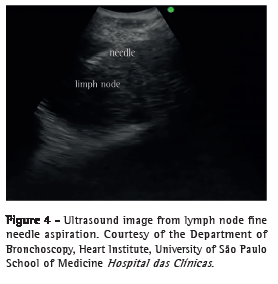

Wang needle (21G) transtracheal/transbronchial aspiration is still often used in conventional bronchoscopy because of its ease of use, safety, and low cost; however, up to 43% of the collected samples are unsatisfactory for diagnosis.(18) Available in Brazil, EBUS needles measure 22G in diameter, are provided with a protective sheath, have an exposure of approximately 4 cm, and have two to three safety locks to reduce the risk of accidents related to aspiration (vessels and other mediastinal structures) and the risk of perforation of the working channel of the device. The needle set includes a dedicated valve that fits into the working channel port of the device, thereby making it possible to connect the needle to the EBUS equipment. Once the needle is introduced into the working channel, it should be pushed until it fully fits into the valve connected to the device and is locked. The sheath should remain exposed until it is seen bronchoscopically, and only then can the safety lock of the needle be released. The needle should be advanced through the tracheobronchial wall in order to aspirate paratracheal or peribronchial lymph nodes or lesions (Figure 4).